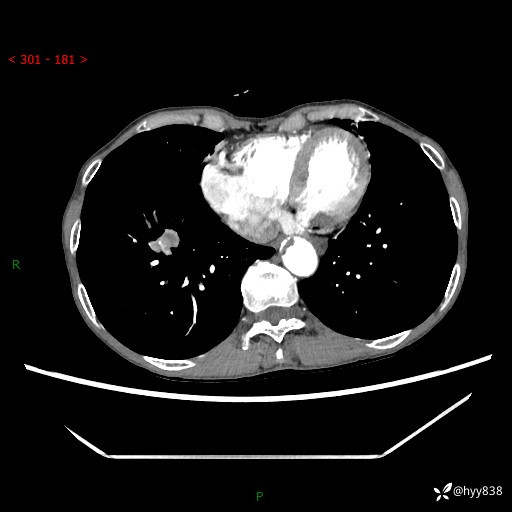

69岁/女,发现肺占位3天余。精彩好病例,请慧诊---(有结果)

【患者信息】:69岁/女

【主诉】:发现肺占位3天余

【现病史及既往史】:患者3天余前因既往肺气肿复查胸部CT发现“右肺下叶结节、双肺多发结节、双肺门及纵膈淋巴结增大”,平素偶有咳白色粘液痰,下肢乏力,无明显低热、盗汗、咯血、胸痛、喘气等不适,今为求明显结节性质遂来我院门诊就诊,门诊以“孤立性肺结节”收治入院。 起病以来,患者精神饮食睡眠一般,大小便正常,体力无明细变化,体重近年来较前下降。

【检查】:胸部CT增强